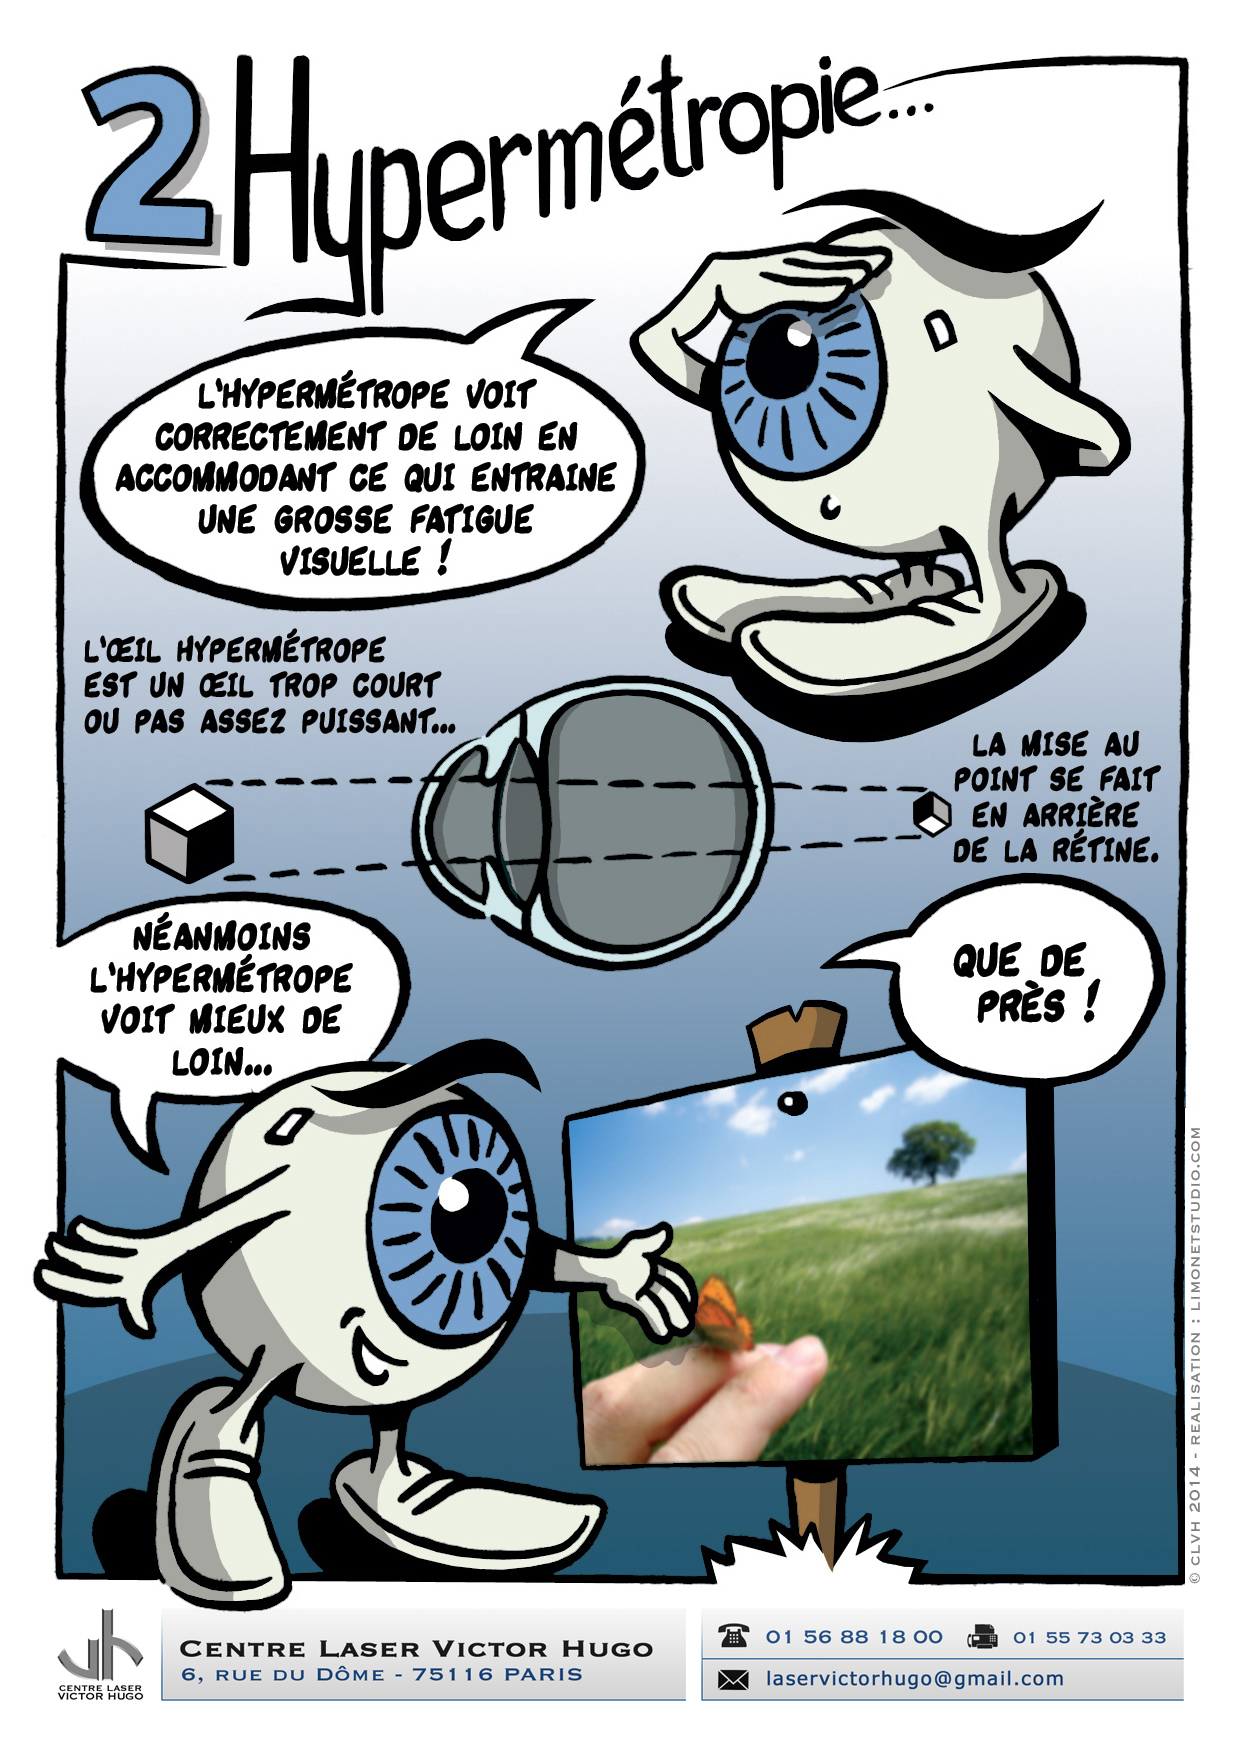

Afin de répondre aux interrogations d'un public de plus en plus intéressé, nous vous proposons cet ouvrage explicatif sous la forme d'une bande dessinée ludique. Cette bédé aborde les troubles de la vision, la chirurgie réfractive (LASIK, PKR et PresbyLASIK), la technique des anneaux et des implants. Cette bébé aborde également l'amblyopie et son traitement orthoptique. Maintenant... à vous de voir !